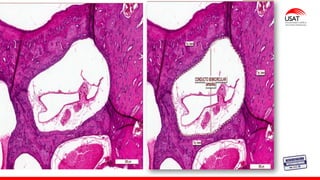

Conducto coclear y

órgano de Corti

Órgano receptor en forma de cuña:

Techo del conductor coclear :membrana vestibular o Reissner

Suelo del conducto coclear: membrana basilar

Membrana vestibular

(de Reissner)

compuesta de dos capas de epitelio escamoso

separadas entre sí por una lámina basal

MEMBRANA TECTORIAL

Una masa gelatinosa rica en proteoglucanos que contiene múltiples filamentos finos semejantes a queratina.

Las células interdentales ubicadas en el limbo espiral secretan la membrana tectorial.

ÓRGANO DE CORTI:órgano receptor de la audición compuesto por células ciliadas neuroepiteliales y

células de soporte

Organo de corti

ESTRIA VASCULAR : epitelio seudoestratificado, 3 tipos de células marginales, basales e intermedias

1. Las células pilares

internas y externas

2. Las células falángícas

3. Las células de Hensen

y del borde.

1. Células vellosas

internas

2. Células vellosas

externas.